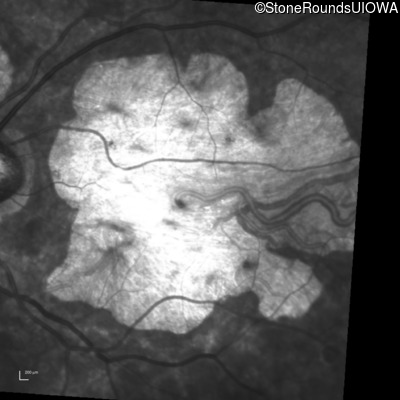

Infrared Fundus Photograph - Right - 20/150

Exemplar